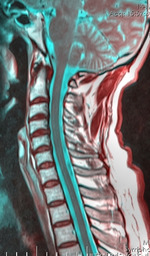

Cervical spine 125153 rgbca 67m.png

Cervical spine

A neurological exam can suggest different motor neuron diseases (such as MMA), but to more confidently distinguish MMA from the diseases it mimics, advanced diagnostic tools are called for. These include exam tools such as Magnetic resonance imaging (MRI), and electromyography (EMG) and nerve conduction velocity (NCV) tests. An MRI examination of the neck would typically reveal - for a positive MMA diagnosis—some constriction of the cervical cord and an abnormal forward extension of the neck, ("loss of cervical lordosis"); pressure by the dura on the nerve cord apparently causes the flattening / narrowing. An EMG test reveals loss of the nerve supply, or denervation, in the affected limb without a conduction block (a nerve blockage restricted to a small segment of the nerve).